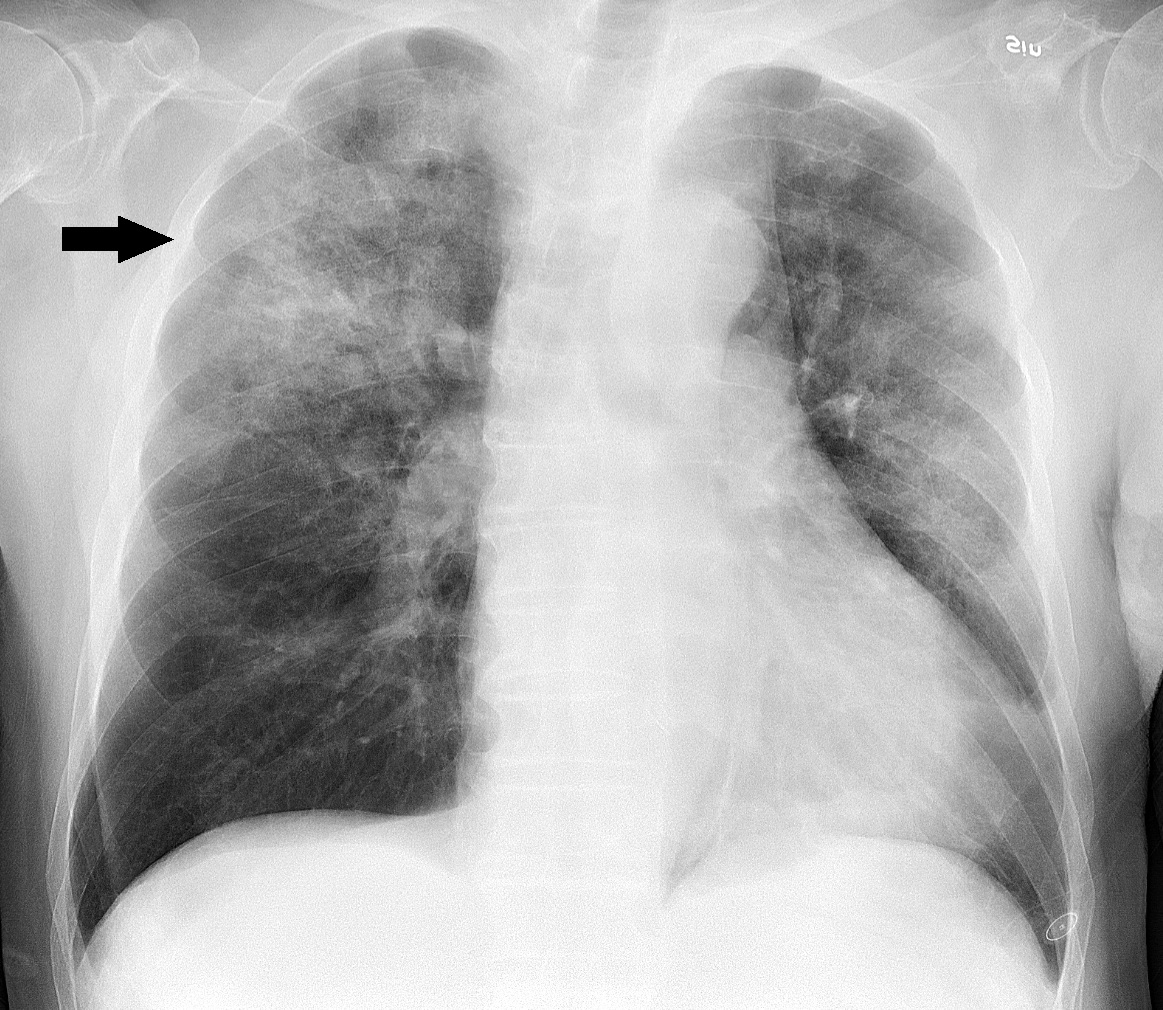

폐렴은 세균, 바이러스, 곰팡이 등이 원인으로 흉부 X-ray 사진에서 폐 부분이 하얗게 염증이 생긴 것으로 알 수 있습니다. 요즘 들어 RS 바이러스, 아데노바이러스, 인플루엔자 바이러스 등 다양한 바이러스가 유행하고 있는데 이것들로 인해 폐렴에 걸릴 수 있습니다. 폐구균, 마이코플라스마 등의 세균 감염도 폐렴의 원인입니다.